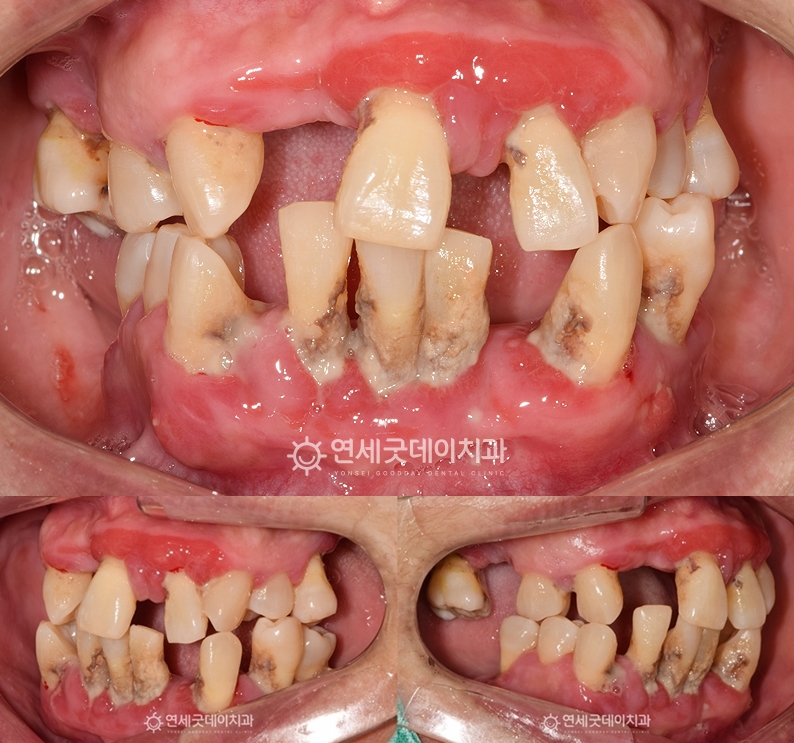

▲ 전체임플란트 치료전 구내

(촬영시기 : 2023년 3월)

치아와 잇몸 주변으로 치석 침착이 심하고 전반적으로 염증이 동반되어 있는 모습입니다.

잇몸뼈가 소실되면서 치아를 지탱하는 힘이 약해져

치아 배열의 불균형과 교합이 붕괴된 상태셨는데요.

이미 다수의 치아가 상당수 손상된 상태로 전체임플란트가 불가피했지만 환자분께서는 자연치아 보존을 희망하셨습니다.

이에 잔존 치아 중 보존 가능한 치아는 최대한 살리고

브릿지임플란트를 통해 기능적, 심미적 개선을 동시에 회복할 수 있는 치료계획을 수립했습니다.